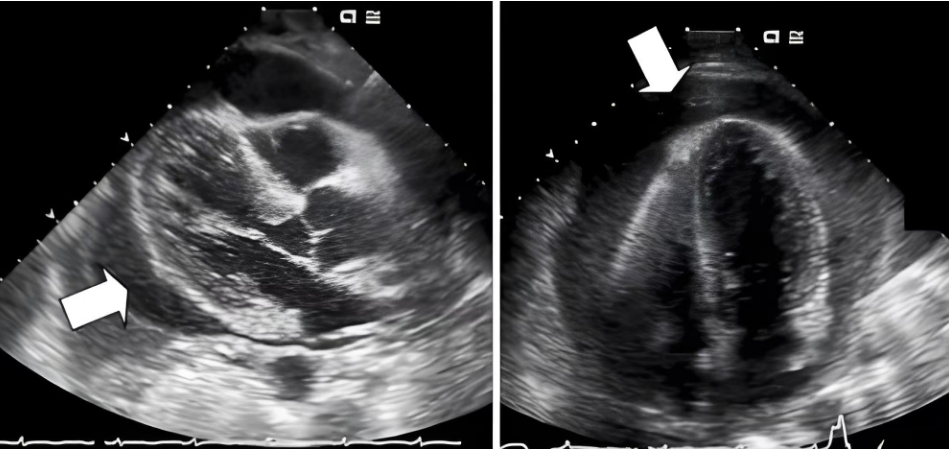

患者入院后不久出现紫绀加重、出冷汗、呼吸困难,逐渐神志模糊,心率极快,血压及血氧饱和度下降;查体:P174次/分,R35次/分,BP47/36mmHg,SPO2:65%,神志模糊,口吐白沫,口唇及面部紫绀,双肺呼吸音粗,闻及湿罗音,心音遥远难辨,四肢厥冷。病情的变化已容不得半点迟疑,急诊科主任蒋劲柏决定在床旁彩超引导下对患者实施心包穿刺术,并随时做好呼吸、循环支持手段的抢救准备。

在取得患者及家属知情同意后,蒋劲柏主任和李承璋医师立即在超声定位引导下行心包穿刺术减压,精准地将穿刺针插入心包腔,并通过软管引流积液。短短 10分钟内,成功完成心包穿刺置管术 ,经心包穿刺引出血性液体500毫升后患者呼吸困难缓解,紫绀消失,血氧饱和度升至99%,心率降至95次/分,呼吸降至21次次/分,血压升至148/126mHg,肢端转暖,意识清醒。术后家属的感激之情溢于言表,经数日精心治疗护理后,患者已于近日好转出院。

蒋劲柏介绍:心包积液是一种常见病症,可能由炎症、心衰、肿瘤或结核等引起,若不及时治疗,可能严重影响循环功能,甚至导致心包填塞。正常情况下,心包腔内液体量为25-30毫升,超过50毫升即视为异常。中到大量积液可引发心包压塞,一旦发生,患者生命垂危。及时的心包穿刺抽液是挽救生命的关键。